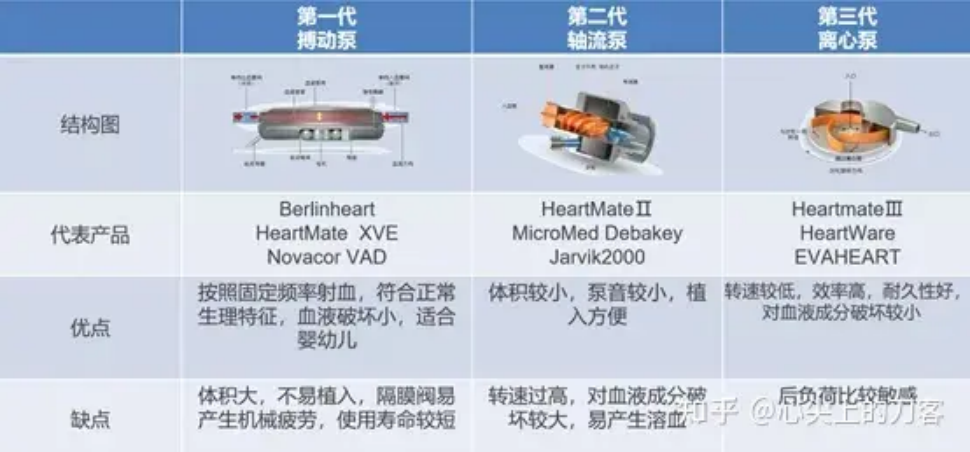

人们在人造心脏上的努力也可以深刻地反映心脏的实际角色。

人工心脏的特点 | 图自[3]

当心脏不能发挥其功能时,就有可能需要人工心脏来替代其功能。人们在设计人工心脏时,最初模仿心脏的搏动得到了第一代搏动泵,但是这样得到的器械体积大,极易损耗。后来从推动血液流动角度得到了第二代轴流泵,结果为了达到原来的血液流动效果,需要非常大的转速,这样容易在人工心脏处对血液有效成分带来很大的破坏。最终第三代磁悬浮离心泵解决了血液成分破坏的问题。

但是人们发现,单纯推动血液流动所需要的功率,远大于心脏本身的工作功率;而定常流推动的方式,不仅不能有效地将营养物质送达到各个组织器官,还将导致心血管组织因脉搏波的消失而逐渐失去弹性,最终产生严重的心血管疾病。目前的人工心脏设计,也需要通过周期性地改变,产生搏动血流,达到心脏原本的效果。